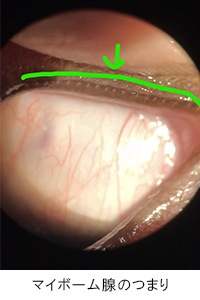

スリットランプ検査にて、マイボーム腺のつまりを確認。圧迫により濁った分泌液を絞り出しました。

| マイボーム腺機能不全と診断。マイボーム腺が目詰まりを起こし、ドライアイ状態になっていました。治療としては眼瞼マッサージや温罨法、ヒアルロン酸点眼などを行います。 完治が目標ではなく、良好な状態を維持することが大切なので、自宅でのケアが大切になります。 |